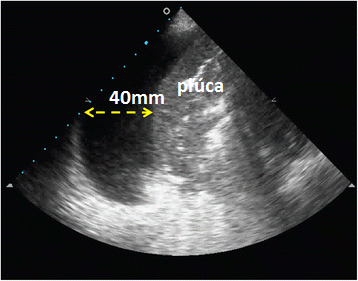

LUS 16. Kvantifikácia množstva pleurálneho výpotku

Ultrasonograficky sa dá identifikovať prítomnosť aj malého množstva výpotku, aj len niekoľko desiatok mililitrov. Otázka na veľkosť výpotku je relevantná predovšetkým v súvislosti s evakuačnou punkciou. Veľké výpotky obmedzujú ventiláciu a môžu mať aj negatívne hemodynamické dôsledky. Niekedy je indikovaná diagnostická punkcia.

Bolo navrhnutých niekoľko spôsobov kalkulácie množstva výpotku. Jednoduchá metóda s dobrou reproducibilitou a prijateľnou presnosťou je metóda podľa Balika a spol. Ležiaci pacienti majú mať zdvihnutú hlavu a hrudník cca do uhla 15°. Výpotok sa zobrazuje v zadnej axilárnej čiare. Sonda sa posúva v transverzálnej rovine na bázu pľúc. Tu sa meria najväčšia šírka výpotku (D) (obr. 16.1.). Merania sa robia na konci exspíria.

Objem výpotku v ml = 20 × D (mm)

Obr. 16.1.